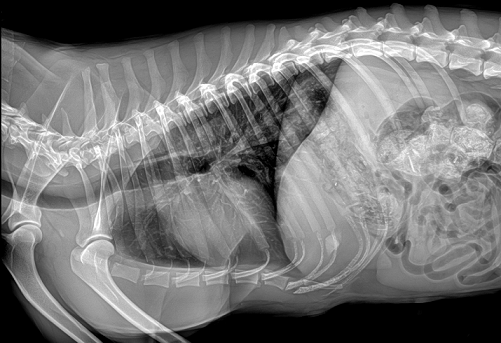

宠物dr影像

普爱医疗宠物dr拍摄的高清照

国产品牌普爱医疗宠物dr采用非晶硅平板探测器,可以令动物影像成像清晰而快速,基本上5s左右就能使动物影像清楚成像且无拖尾现象,而且分辨率高,极限空间分辨率可达到5.0Lp/mm;

同时,宠物影像成像尺寸较大,成像尺寸可达43cm x 43cm,并且以DICOM格式储存数据,极大的方便了医疗工作者们追踪检查时使用。同时还支持窗宽、窗位、放大、旋转、正像和负像转换等显示功能。如果您想购买普爱医疗宠物dr,或了解具体技术参数,欢迎联系我们。